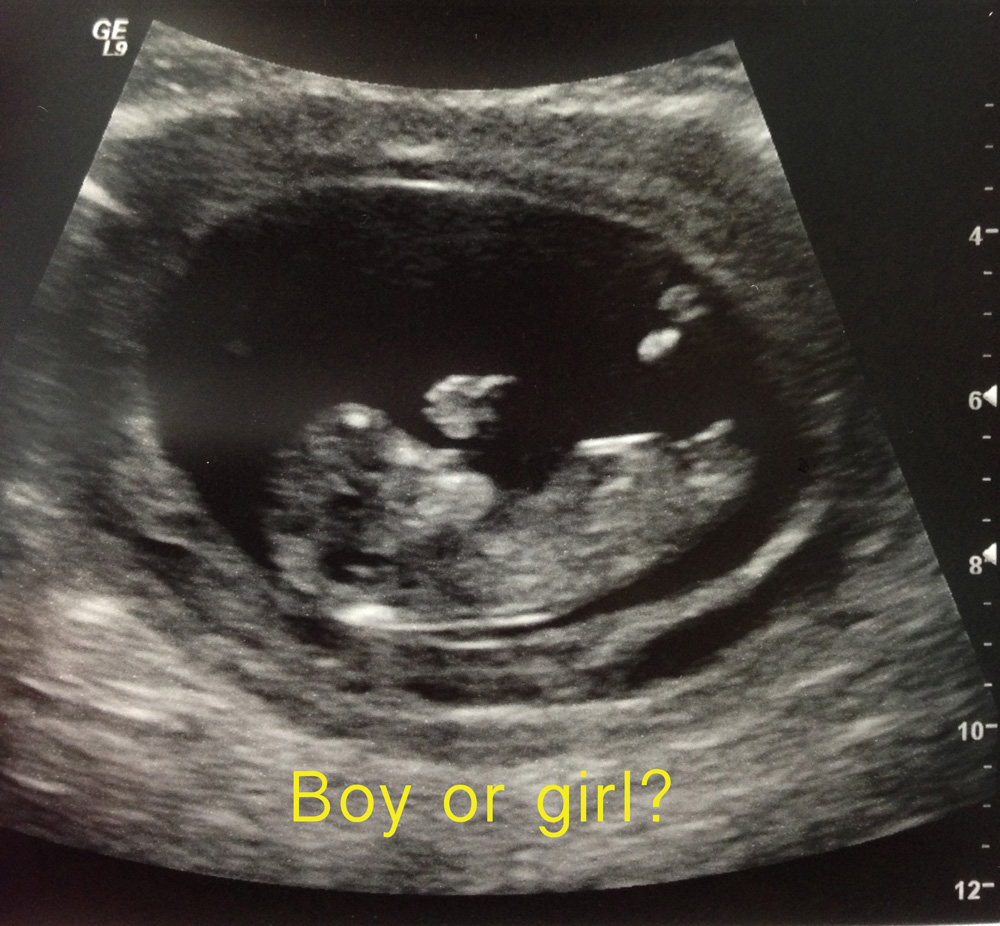

I am so excited to know if this is a boy or girl! We already have a son so as long as baby is happy and healthy that's what's important but I would love a pink bundle as it's definitely our last baby.

I have my private gender scan scheduled for 17 weeks on August 6th, but the wait is killing me!!! Would love your opinions to help me pass the time. Thank you in advance!

Attachment 12443